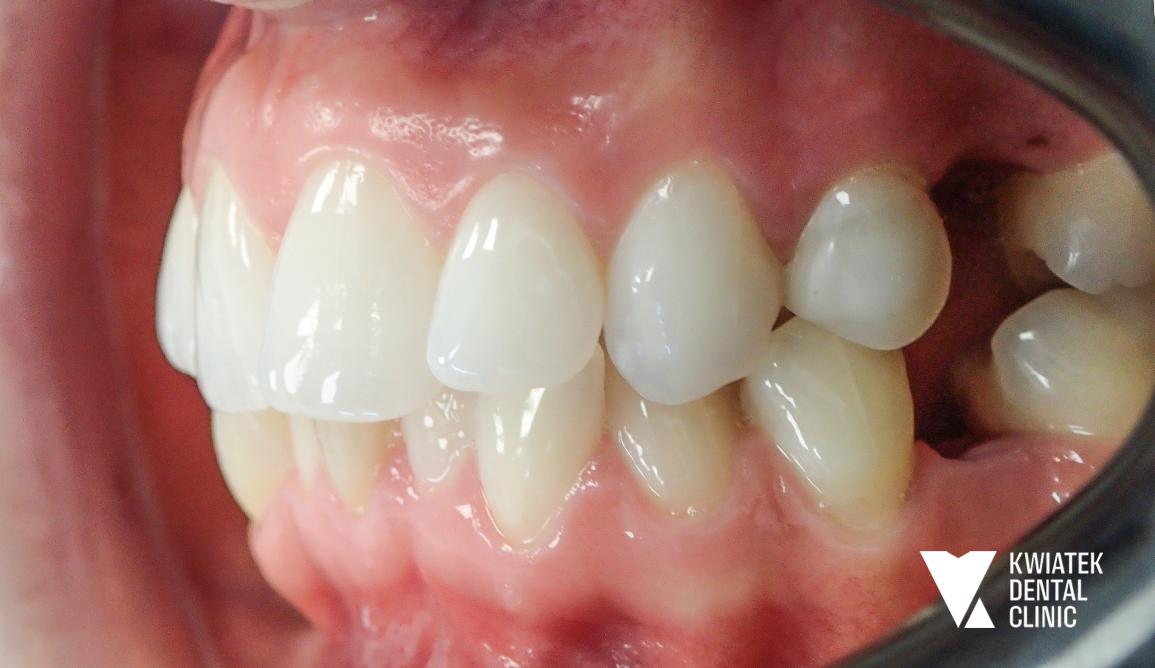

PO

Efekt końcowy to pełna metamorfoza uśmiechu zarówno pod względem zdrowotnym, jak i estetycznym.

Uzyskano:

• prawidłowe ustawienie zębów w łukach

• zamknięcie przestrzeni po ekstrakcjach

• poprawę relacji zgryzowych

• naturalny, harmonijny uśmiech